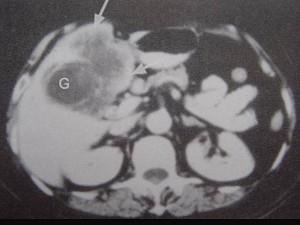

问题 男,68岁,上腹部隐痛二月余,CT检查如图,最可能的诊断是 ( )

选项 A、胆囊息肉 B、胆囊区转移瘤 C、胆囊癌(肿块型) D、胆囊腺肌增生症 E、慢性胆囊炎

答案 C